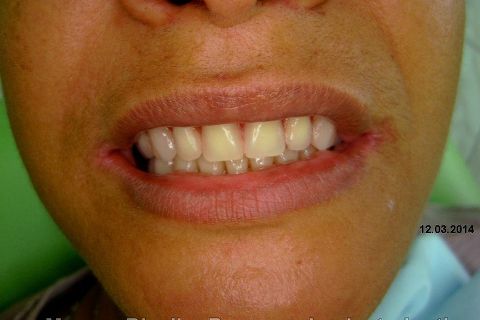

Atualização do caso clínico que já postei, "REABILITAÇÃO EM MAXILA ATRÓFICA COM IMPLANTES", um caso que inclui expansão do rebordo estreito com cinzel e martelo, expansores rosqueáveis, enxerto e instalação dos implantes distais inclinados tangenciando seio maxilar. Inclui esvaziamento do forame nasopalatino e preenchimento com biomaterial para instalação de dois implantes próximos dele. Cirurgia realizada em única sessão, com instalação dos 6 implantes. Para os colegas que não conheceram e/ou esqueceram da apresentação, este é o resumo do caso na fase cirúrgica.http://www.youtube.com/watch?v=BtvexFexRPA&hd=1

FASE PROTÉTICA DA REABILITAÇÃO EM MAXILA ATRÓFICA...incluindo a reabertura, instalação dos minipilares e PTR provisória reembasada sobre os cilindros de proteção.